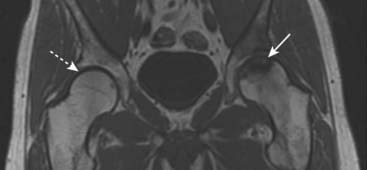

image

Figure 21-8 Avascular necrosis, MRI.

A T1-weighted coronal view of both hips demonstrates normal high signal from the fatty marrow in the right femur (dotted white arrow) but decreased signal in the left femoral head extending to the subchondral bone of the left hip joint (solid white arrow). The joint space is preserved.

Figure 21-9 Avascular necrosis of the left femoral head in a patient on long-term steroids for lupus erythematosus.

A close-up view of the left femoral head shows a zone of increased sclerosis in the superior aspect of the femoral head (solid white arrows), a characteristic finding of avascular necrosis of the head. The linear, subcortical lucency (solid black arrow) represents subchondral fractures seen with this disease, called the crescent sign. Notice that the disease is isolated to the femoral head and involves neither the joint space nor the acetabulum, i.e., this it is not an arthritis.